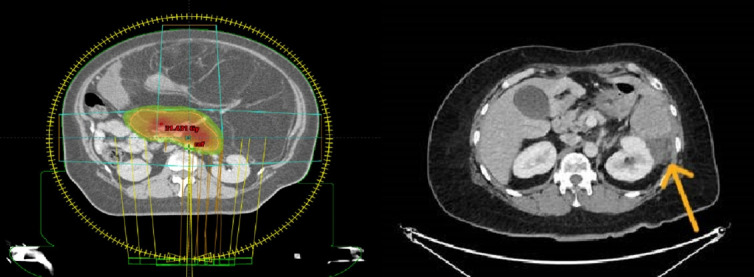

Materials and methods: This is a single-center, prospective, non-randomized feasibility study. SCRT was administered via image-guided volumetric modulated arc therapy, consisting of 5 fractions of daily radiotherapy followed by immediate surgery. As a starting dose, patients were prescribed 25 Gy in 5 fractions. For the escalation stage, patients were prescribed 30 Gy in 5 fractions. Only the presumed threatened surgical margins were delineated for large tumors.